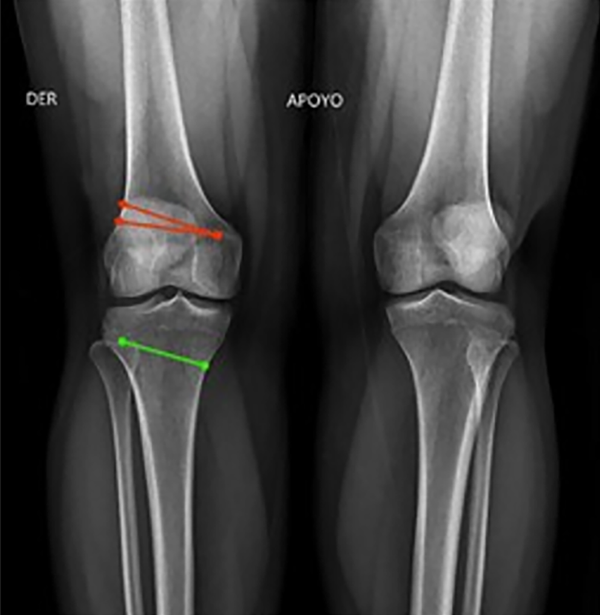

Figura 4: Ángulo femoral distal lateral mecánico (mLFDA): mLDFA y MPTA bilateral, se observa del lado izquierdo una deformidad en varo del fémur 92° (normal 85-90°) y la tibia 84° (normal 85-90°). Lado derecho con una deformidad en varo del fémur 92° y la tibia 87° en valor normal.

Figura 5: JLCA bilateral de 2° (valor normal 0-2°).

El test de mal alineamiento continúa con dos anexos: el 1 se realiza para descartar la subluxación de la articulación de la rodilla y el anexo 2 evalúa la alineación condilar.

Figura 6: Se observan el punto central de la línea de orientación articular, en rojo el de fémur distal y en verde de tibia proximal, y la línea azul muestra que el anexo de subluxación está en 0 mm (rango normal: 0-3 mm).

Figura 7: Se observa en líneas roja y verde la línea articular de cada cóndilo femoral y cada platillo tibial, se evidencia que son colineales, por lo cual no hay una incongruencia articular.